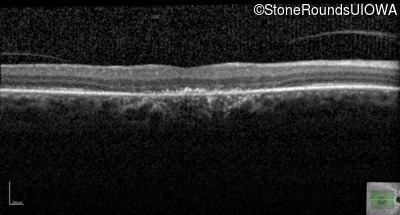

Optical Coherence Tomography - Left - 20/15 -1 sc

Exemplar / OCT Stack